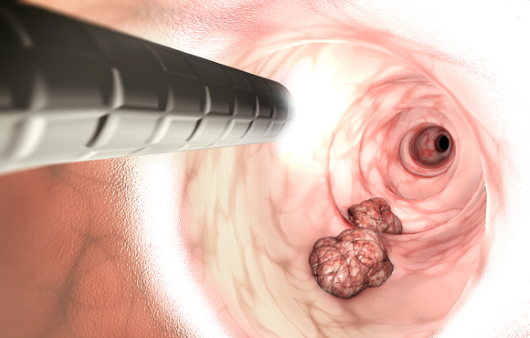

대장내시경 검사 후 나이에 상관없이 고위험군은 3년 후, 저위험군은 5년 후 검사를 권고해요. 대장용종에서 대장암까지의 발병 기간은 5 ~ 10년 이므로 적어도 5~10년 간격으로 재검사는 필수로 필요해요.

하지만 본인의 인체는 본인이 챙겨야 하기에 위암이나 대장암 가족력이 있는 경우 그보다 일찍 정기 검진을 받는게 좋으며 이유할 수 없는 체중 감소, 식욕 부진, 배변, 메스꺼움 중 검은색 또는 묽은 변이 나타나면 진단을 위해 대장 내시경 검사를 권장하며 내시경 치료가 즉시 가능하기에 질병의 조기 발견이 중요해요.